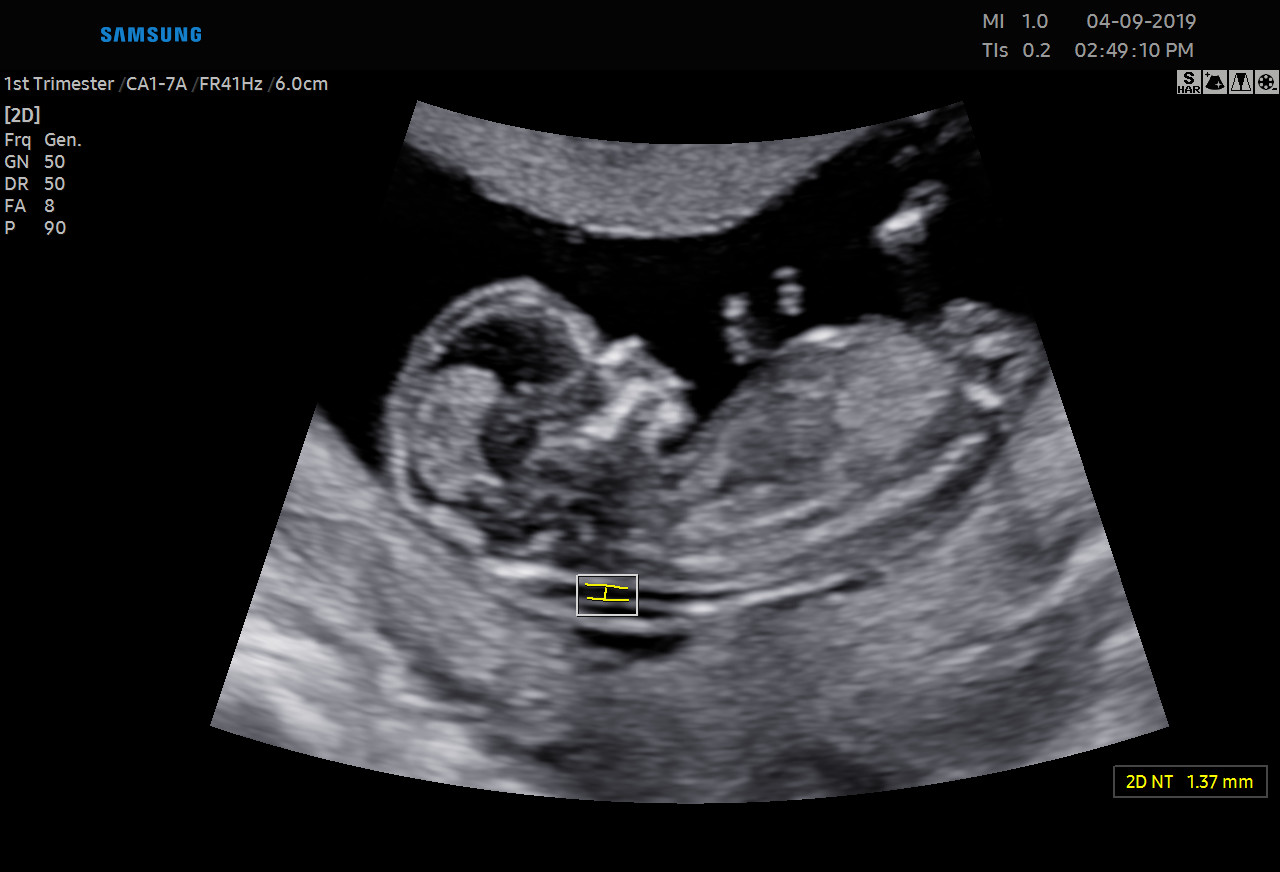

Diagnostykę obrazową przeprowadzamy z wykorzystaniem sprzętu Samsung HERA W9. To najnowszy aparat klasy premium – z kompletem głowic USG wysokiej rozdzielczości w tym głowicą USG 3D/4D. Doskonała jakość obrazu przekłada się na wiarygodność wyników.

• USG ginekologicznym i w czasie ciąży wtym 3D/4D.

Ponadto jesteśmy w stanie zmierzyć przepływy w naczyniach u kobiet ciężarnych oraz płodu.